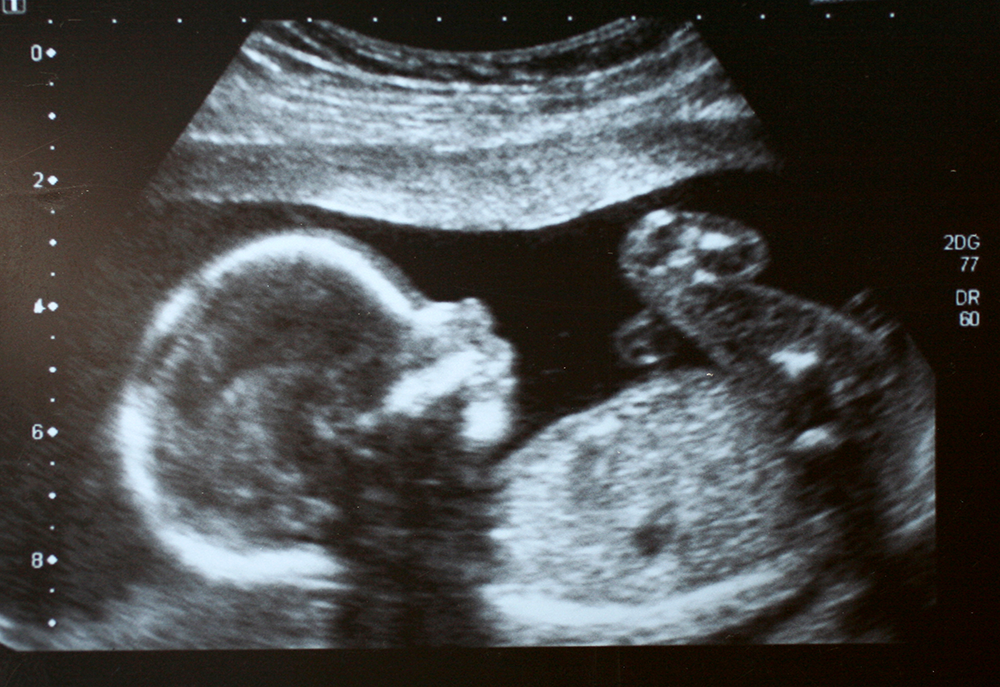

If there had been proper debate over the proposal, rather than introducing it alongside 1,482 other amendments, parliamentarians might have spotted the flaw: the proposed legislation will enable sex-selective abortions. The NHS normally delays the point at which parents are entitled to know their child’s sex until the 20-week scan, shortly before abortion currently becomes illegal. As there will no longer be legal penalties for any abortions, there will no longer be any way to prevent parents from terminating a pregnancy once they find out the child is a girl.

There is also wider evidence that sex selection occurs in the UK, even if it is difficult to count. Some parents already bypass the NHS restriction by using private tests – which can tell them the sex of a child as early as seven weeks into gestation. These private tests cost around £200. A 2018 BBC investigation found that they were being used to inform sex-selective abortions.